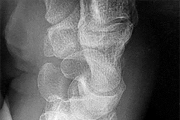

A 62-year-old male of East Asian descent presents with progressive myelopathy. His imaging is shown. Which of the following specific CT findings is the strongest independent predictor of a dural tear during an anterior cervical corpectomy and decompression for this condition?

Options:

Correct Answer: The 'double-layer' sign

Explanation:

The image indicates Ossification of the Posterior Longitudinal Ligament (OPLL). The 'double-layer' sign on a CT scan is highly specific for dural ossification and represents a significant risk for dural tears during anterior decompressive surgeries. It consists of anterior and posterior hyperdense ossified rims separated by a central hypodense non-ossified ligament.